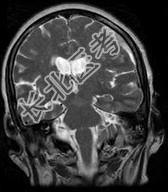

- 单项选择题女,71岁, 头晕,言语模糊, 2周前被摩托车撞伤,结合MRI图像选择最可能的诊断 ( )

D、亚急性硬膜下血肿

E、慢性硬膜下血肿